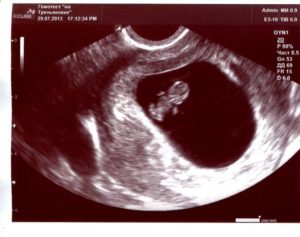

УЗИ на 9 неделе беременности

На УЗИ плода на 9 неделе определяется толщина плаценты и общее состояние пуповины. При помощи допплера, будущая мама может отметить частоту сердечных сокращений малыша. Хотя многие внутренние органы уже достаточно развиты, это не всегда можно увидеть на УЗИ на 9 неделе.

Внутренние органы крохи еще могут выступать в виде пупочной грыжи, но нет повода для беспокойства, ведь это совершенно нормальное явление.

Определить пол будущего ребенка на УЗИ ещё нельзя, однако, существуют другие способы узнать пол своего малыша. О достоверных способах мы говорили в этой статье.